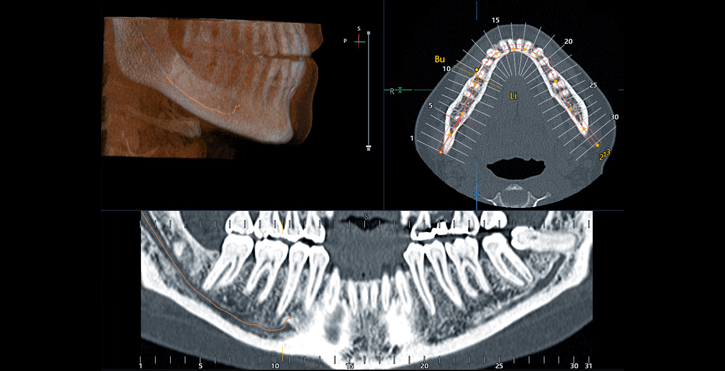

1. CT Scan

KavoScan is a powerful imaging technology that creates a 3D computer model of your bone structure. We can use this model to precisely plan your dental implant surgery before we begin. It’s almost like having the first part of your surgery performed on the computer.

CT Dental Scan allows us to find the ideal placement for your dental implants without guesswork and without additional cutting. It allows us to get your dental surgery right the first time, so there’s no need for multiple procedures. The scan is taken at our office and takes only a few seconds with very minimal radiation (unlike medical grade CT scans).